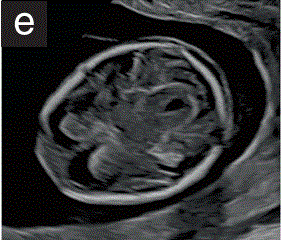

(3.4)大脑区域主要由侧脑室构成,侧脑室看起来很大,其后部三分之二几乎被轻微不对称的回声脉络丛填满(图2d)。

胎儿mt是什么检查什么疼吗【文献学习/规范指南】ISUOG实践指南(2023更新): 11-14周胎儿超声检查(全文)_https://www.jmylbn.com_新闻资讯_第9张

图2 11+0至14+0周时,可作为详细胎儿超声检查的一部分获得的解剖图。

(d)经脑室平面的胎儿头部横断,显示正常的椭圆形头部,胎儿颅骨骨化,半球间镰将胎儿大脑分成两个相对对称的半球,脉络丛几乎填满后三分之二的侧脑室(蝶形征)。

(3.5)大脑半球看起来是对称的,由半球间裂和镰分开。大脑皮层非常薄,最能观察到到它的前部,衬着充满液体的大心室(图2e)

胎儿mt是什么检查什么疼吗【文献学习/规范指南】ISUOG实践指南(2023更新): 11-14周胎儿超声检查(全文)_https://www.jmylbn.com_新闻资讯_第10张

(e)经丘脑平面的胎儿头部横断切面,显示正常的椭圆形头部、胎儿颅骨骨化、半球间镰、丘脑、侧脑室和大脑脚。